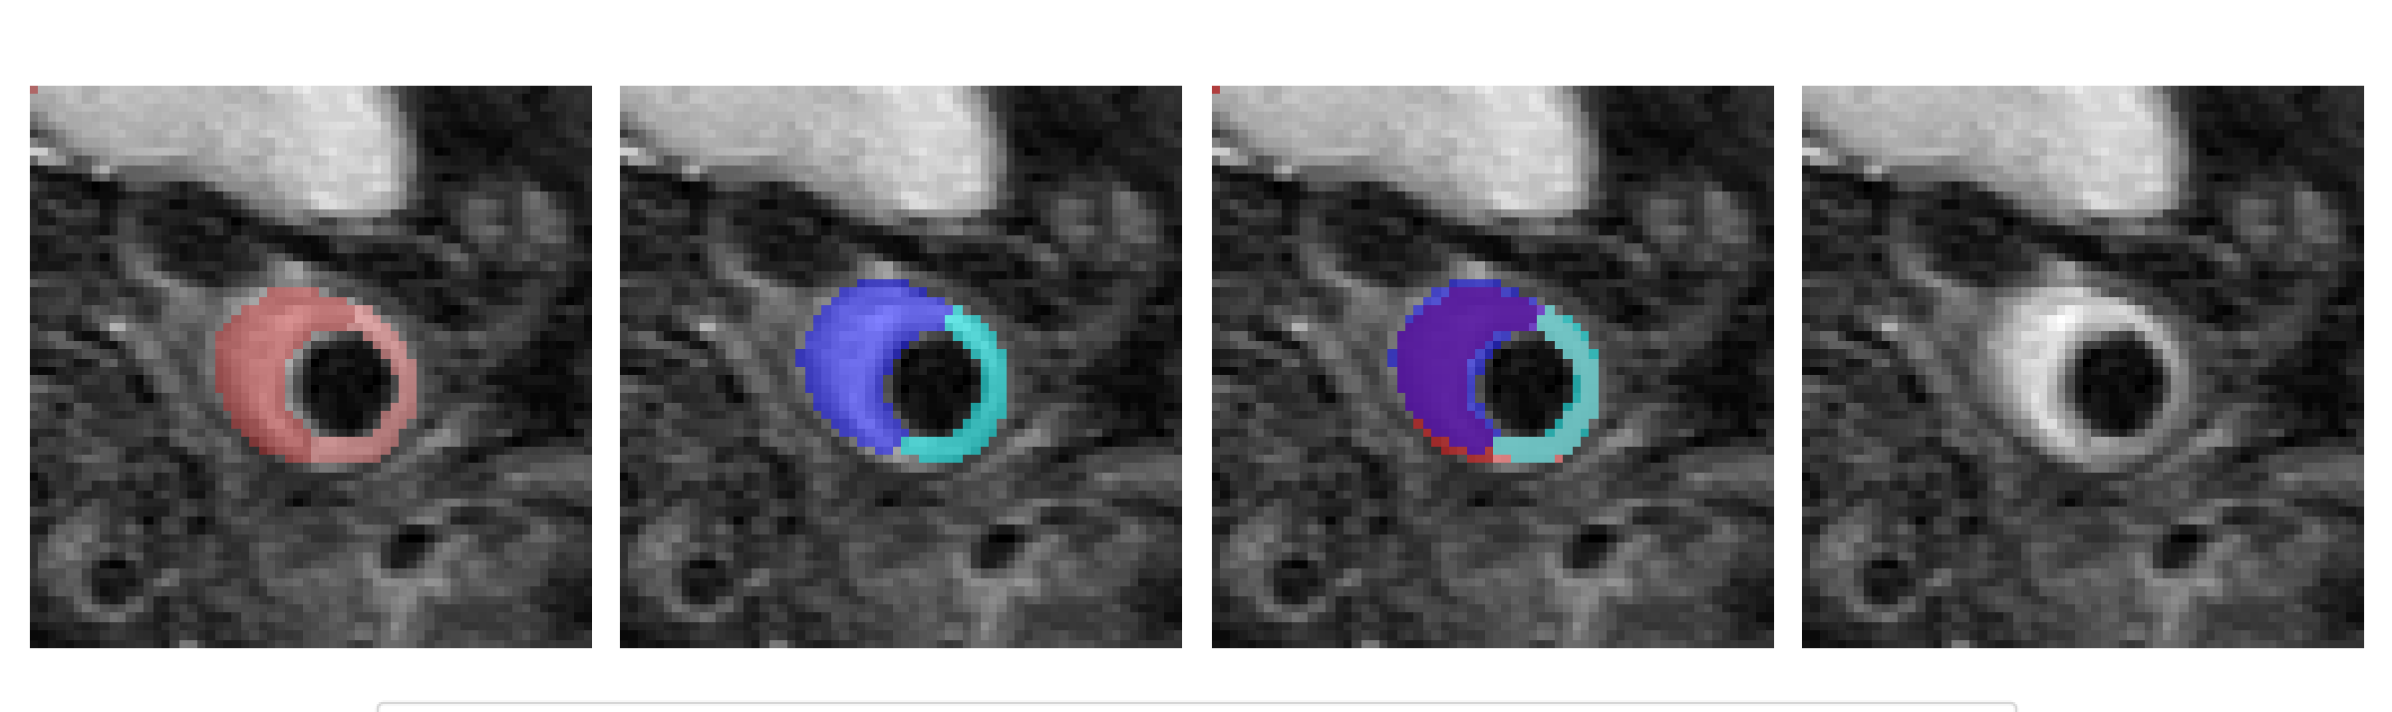

For multiclass segmentation, Figure 8 displays representative output masks generated by our U-Net model using late fusion, where again image slices from 16 patients were used for training, slices from 4 patients for validation and slices form 4 patients for testing. Similar to the binary case, we observed a good coverage of the predicted masks and the ground-truth annotations provided by radiologists. Again, our U-Net model often seems to reflect the structure of the vessel more accurately compared to the ground truth mask.

We also extended our analysis of the fusion strategy to the multiclass segmentation task, where each pixel was assigned to either background, vessel wall or plaque. Table 3 presents the segmentation scores of our U-Net model and a basic U-Net model using bottleneck and input fusion. For our U-Net, input and bottleneck fusion provided similar results, underscoring the robustness under the fusion of sequences. The basic U-Net model together with bottleneck fusion was superior over input fusion and over our model architecture in contrast to the binary case. In order to better understand this observational mismatch of binary and multiclass segmentation, we visually analyzed predictions from both basic and our U-Net using late fusion. Figure 9 displays some exemplary outputs. The segmentation masks from the basic U-Net match the ground truth labels more accurately, while our model misclassified plaque according to the ground truth masks. However, the wrong plaque regions from our predictions show a thickened artery wall and high intensities. This suggests that the identified plaque regions not necessarily indicate a misclassification but may be the result of inaccurate ground truth labels, which would explain the worse segmentation results of our U-Net model.